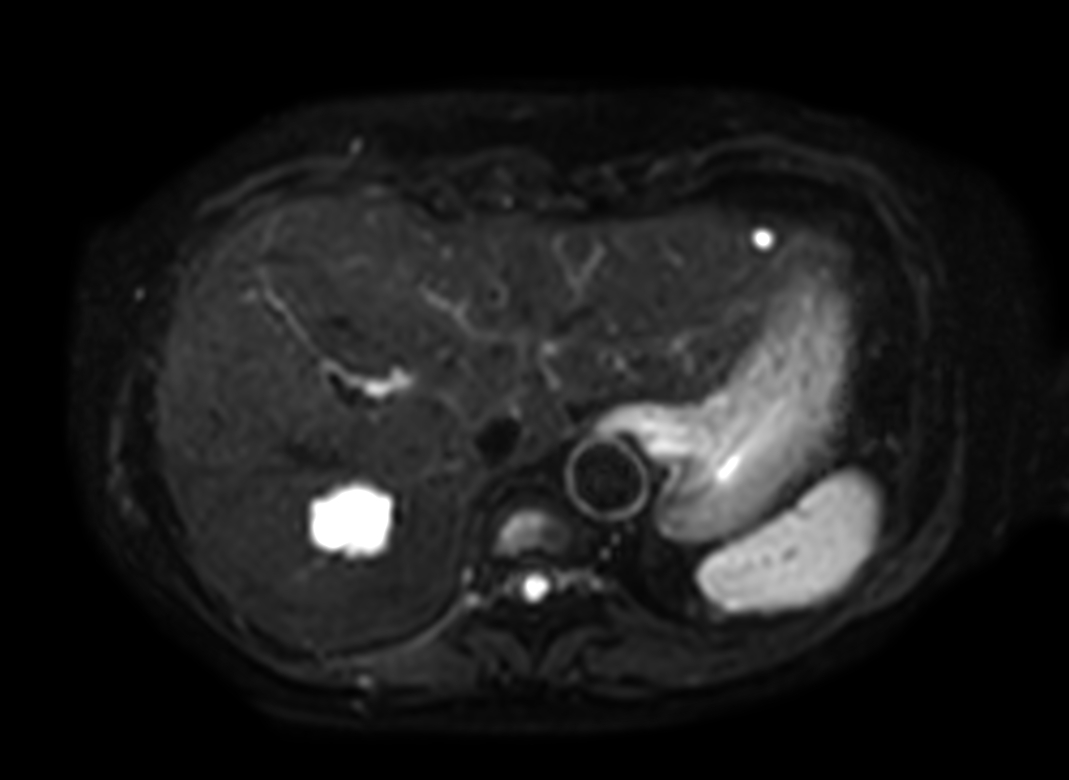

Axial DWI (b8, Black Blood)